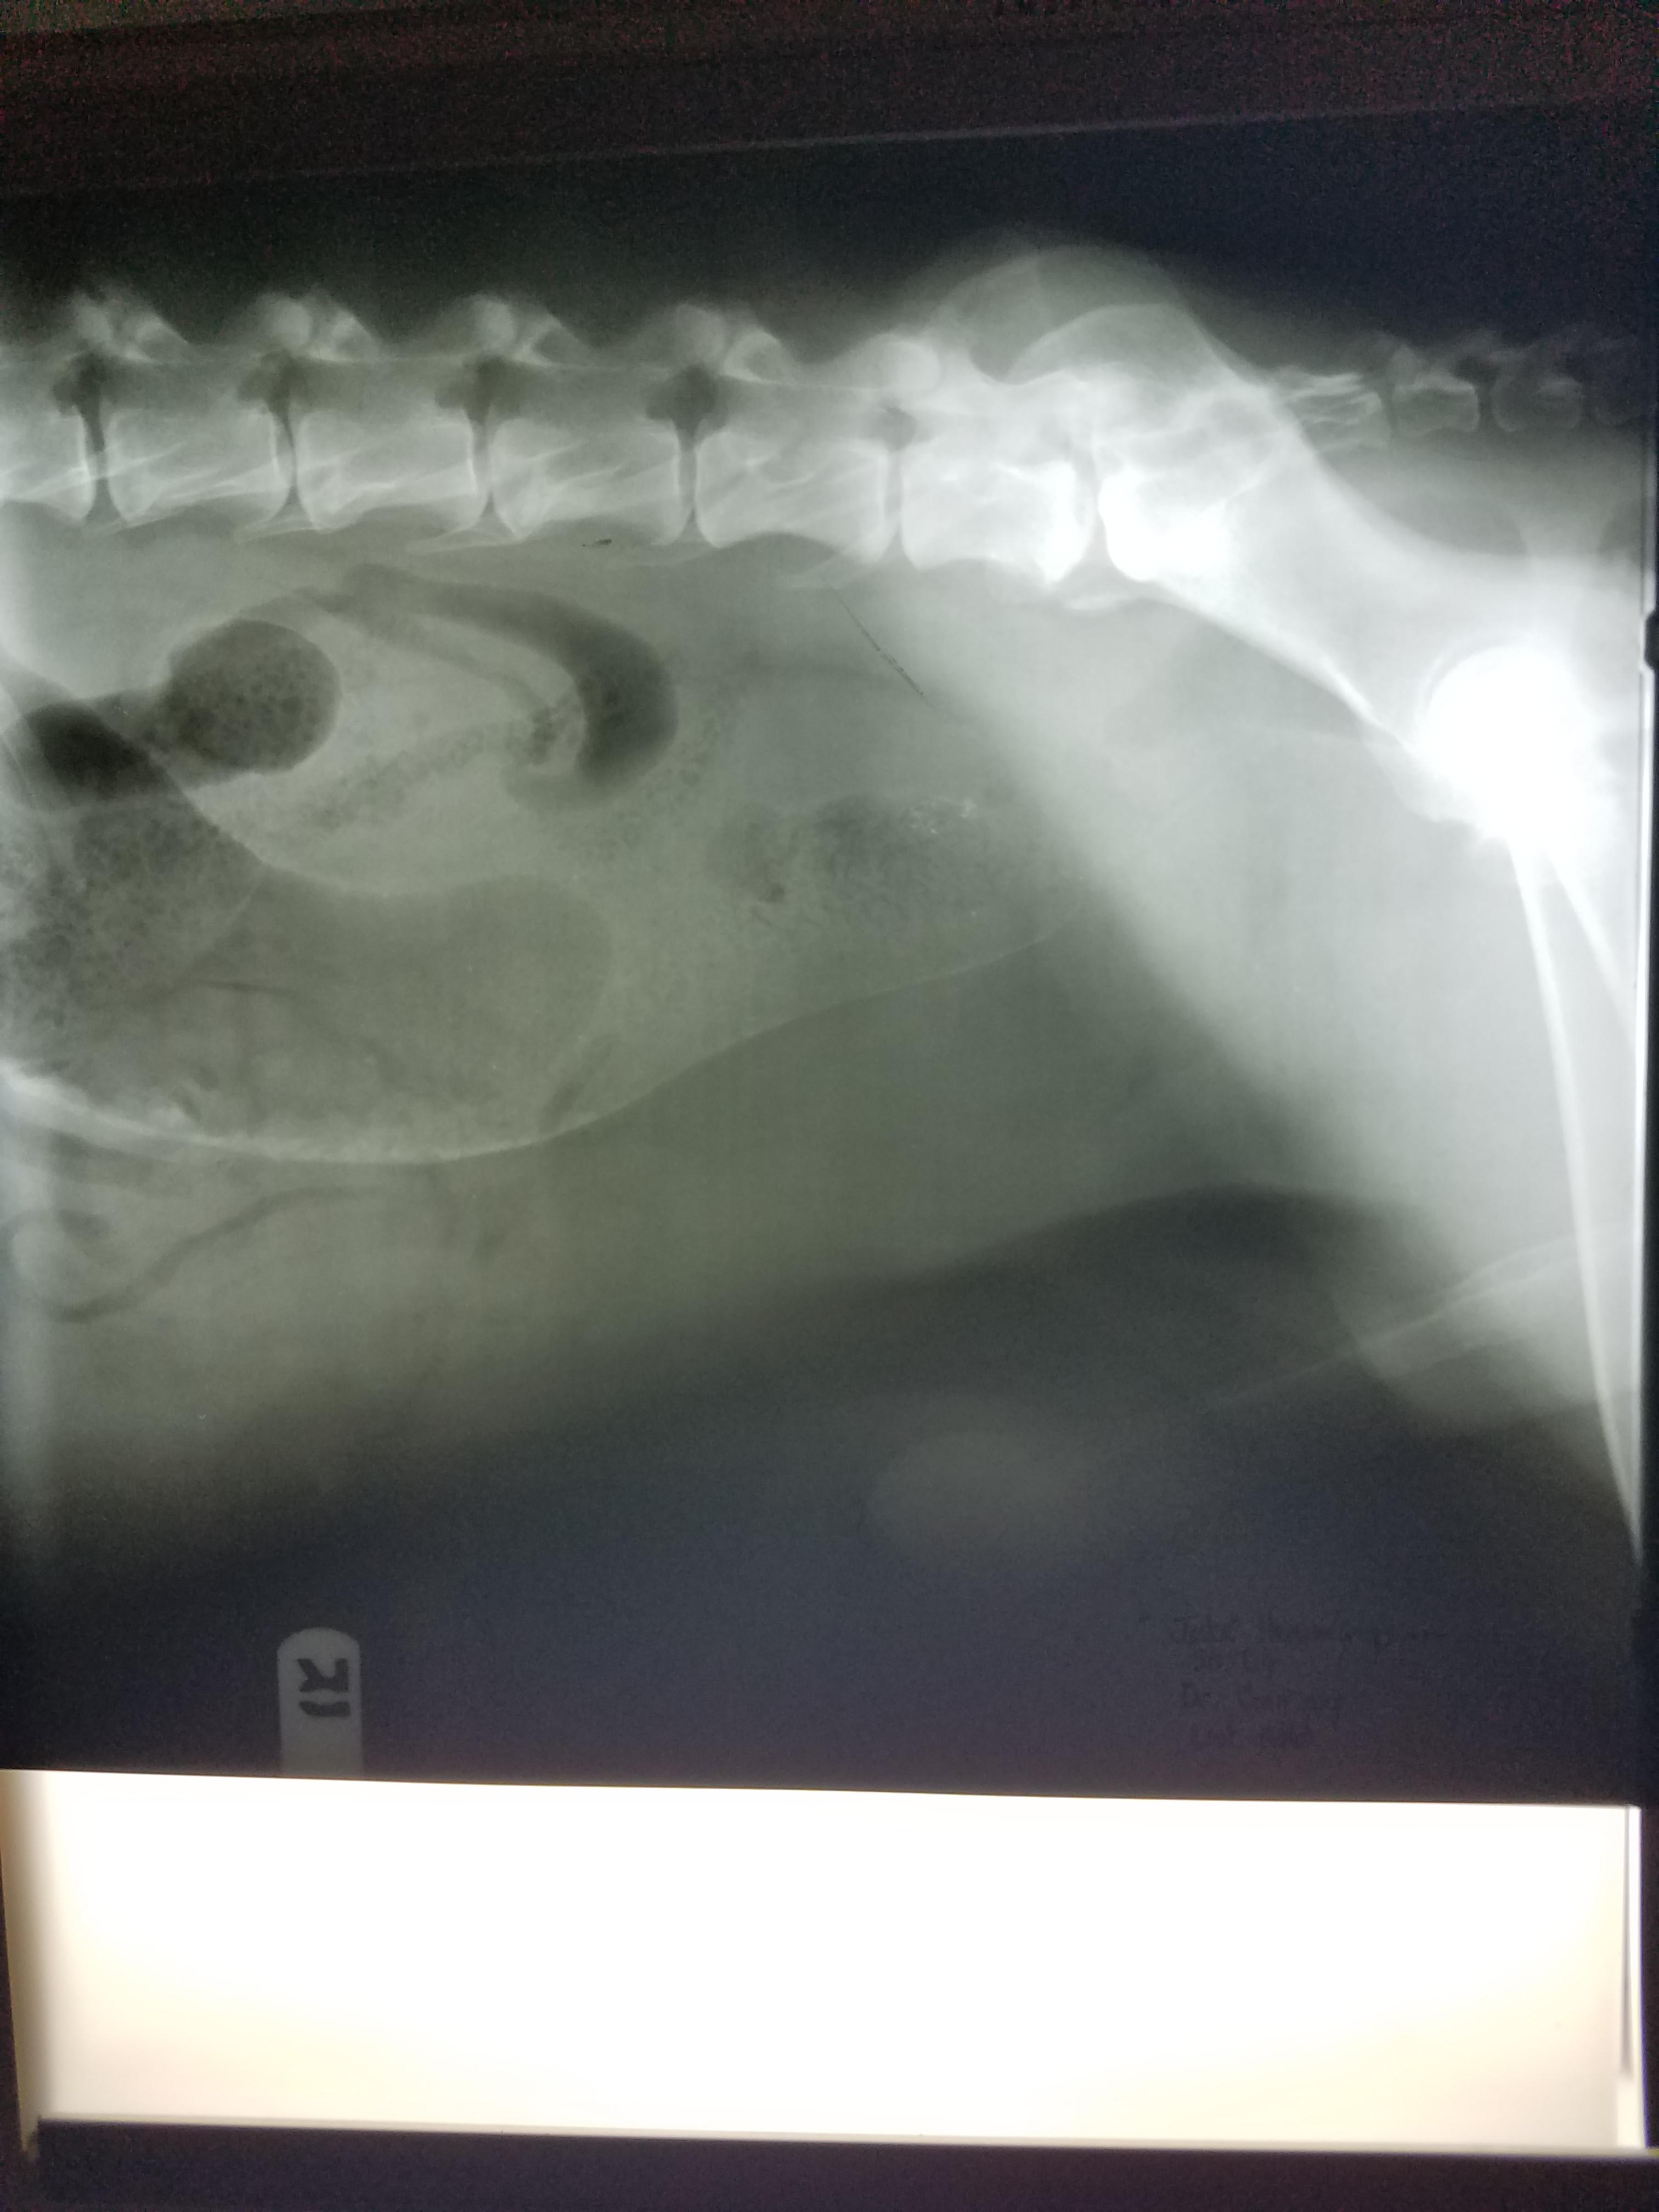

Getting diff answers. Notes from exam. Large mass encompassing colon, air distended, fistulas,could be rupturing bladder or prostate, blood pass from penis,rear right leg edema, testicles swollen, circulation compromised, diagnosed neoplasia colon,rectum possibly prostate. Recommend euthenasia.. A Dr here just told me he didn't see anything other than gas/ feces. Blood work and x rays attached